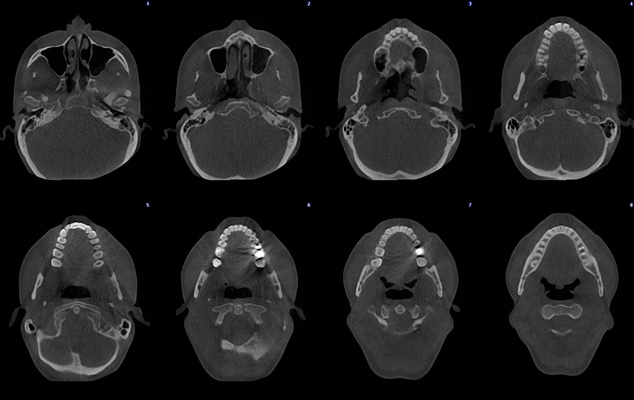

Ultra low dose image - Orthodontic case

Planmeca ProMax 3D - FOV Ø 85 x 50 mm. - Voxel size 400 µm - Effective patient dose 7.9 µSv

Planmeca ProMax 3D - FOV Ø 85 x 50 mm. - Voxel size 400 µm - Effective patient dose 4.0 µSv